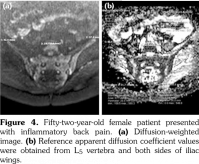

Sacroiliac joints were assessed according to ankylosing spondylitis criteria. Before evaluation of standard MRI protocol, patients’ information was removed from images. Afterwards, two experienced radiologists evaluated the images for the presence of inflammatory activity twice at separate sessions to assess interobserver variability. Following the examination of T2-weighted SPIR, contrast- enhanced T1-weighted SPIR, and DWIs at b values of 600 s/mm2, two radiologists and rheumatologists reached a consensus on the disease activity in the light of positive features of Berlin criteria. The DWIs were transferred to a separate workstation (Phillips, Extended MR workspace, 2.6.3.2.HF3, Netherlands). ADC maps were generated. T2-weighted SPIR images, contrast-enhanced images and diffusion-weighted images with ADC maps were put on the screen side by side. In the disease group, the hyperintense lesions on T2-weighted SPIR images and enhanced focuses on contrast- enhanced images were noted and the same lesions were marked on DWI images and ADC map. A circular ROI with a range of 40-75 mm2 was placed in those areas. In the control group a circular ROI was placed in the subarticular area of joints. Also, the same process was performed for the normal-appearing bone marrow areas near the joints of the disease group (Figure 2). Four standard measurements were conducted from each joint, including two on sacral and the other two on the iliac side for all patients (Figure 3). Additionally, two measurements were conducted from the fifth lumbar vertebra and one from each iliac wing (Figure 4). All measurements were performed twice. ADC values were expressed as square millimeters per second. The r-ADC ratio was calculated by dividing ADC value of subchondral bone or inflammatory lesions to ADC values of the fifth lumbar vertebra and iliac wings.

Normalized ADC, known as r-ADC, which is calculated by the formula ADC lesion/ADC reference site(9) is used to normalize the ADC value and eliminate the individual differences. A number of studies have been performed by using r-ADC values for characterization of focal pancreatic lesions,(22) in liver fibrosis,(23) for estimating histological grade of vesical urothelial carcinoma,(24) monitoring the development of brain infarction,(25) and assessing benign and malignant breast lesions.(26) To our knowledge, no study has been conducted by using r-ADC values performed on the musculoskeletal system so far. In our study, we used L5 vertebra or iliac wings as the reference organs to eliminate individual differences of bone marrow of patients as well as the differences arising from the acquisition protocol and signal analysis. The patients’ own normal bone marrow was chosen as the reference standard and a proportional value was obtained for each patient. We saw that normalized ADC values were able to detect active sacroiliitis as well as the conventional DWI. r-ADC measurements of lesions could discriminate the disease with the reference site chosen as either vertebra or iliac wings. In r-ADC values calculated with the L5 vertebra, there was no significant difference between unaffected portions of bone marrow areas in patients with sacroiliitis and mechanic back pain whereas the r-ADC remained still higher than the normal bone marrow areas in patients with sacroiliitis or mechanic back pain. So, we think that this method may be used to detect real active lesions by normalizing unaffected portions of sacroiliitis patients that were also higher in DWI without normalizing method. As a consequence, we think that L5 vertebra is a more useful reference organ in calculating r-ADC than iliac wings. Furthermore, because of the difficulty in measuring the ADC values of iliac wings owing to the narrow zone to put the ROI in MRI sections, choosing the L5 vertebra as the reference organ is much easier in addition to the advantage of having the similar architecture with the bones of the sacroiliac joint. Also, AUC values for lesions calculated with r-ADC with the reference organ chosen as L5 vertebra were higher than the AUC values for lesions calculated with r-ADC with the reference organ chosen as iliac wings. This method may be safely used to detect active sacroiliitis in individuals that have pathologic conditions causing generalized bone marrow edema that might affect subchondral bone marrow ADC values. By this way, quantification of active lesions can be performed more accurately. We did not have any patient with generalized bone marrow edema; however, particularly younger patients had more active bone marrow. Still, the number of those patients was not sufficient to conduct a statistical analysis to compare with the patients with less active bone marrow edema. Further studies are required with younger and older populations to compare vertebral bone marrow and r-ADC values of sacroiliac joints of the groups to understand effectivity of r-ADC values.